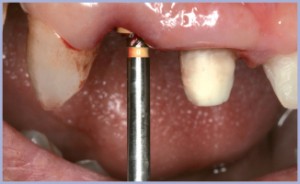

L’articolo tratta la riabilitazione del settore frontale superiore. Il 12 è stato estratto con delicatezza (figg. 1, 2, 3), la lesione periapicale è stata accuratamente rimossa ed una ispezione dell’alveolo post-estrattivo ha messo in evidenza quattro pareti ossee molto ben rappresentate sia in spessore che in altezza.

Con la fresa pilota è stato necessario ritracciare la direzione dell’alveolo destinato ad accogliere l’impianto, variandola rispetto a quella dell’alveolo post-estrattivo già presente.

L’obiettivo era quello di posizionare l’impianto stesso ben accollato alla parete palatale e al tempo stesso di creare uno spazio vuoto fra l’impianto e la parete ossea vestibolare, in cui il coagulo ed un eventuale riempitivo potessero dar luogo ad una rigenerazione ossea.

In tal modo è possibile ridurre al minimo il rischio di una perdita ossea vestibolare, fisiologica dopo un’estrazione.